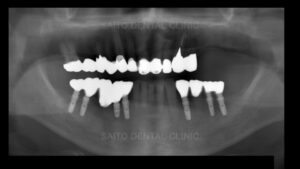

そこでまずは本来の噛み合わせの高さに戻すためにマウスピースを製作しまず上の歯を揃える計画を立てます

そして奥歯にインプラント治療をしていきますが右下の部分は顎の骨の中の神経付近まで

そこで右下は手前の歯をインプラントで引っ張って周囲の骨ごと引っ張ってその手前に

インプラントを植える治療方法としました

矯正治療後インプラントに被せ物をし、上の顎は予算を相談し部分義歯を装着しました